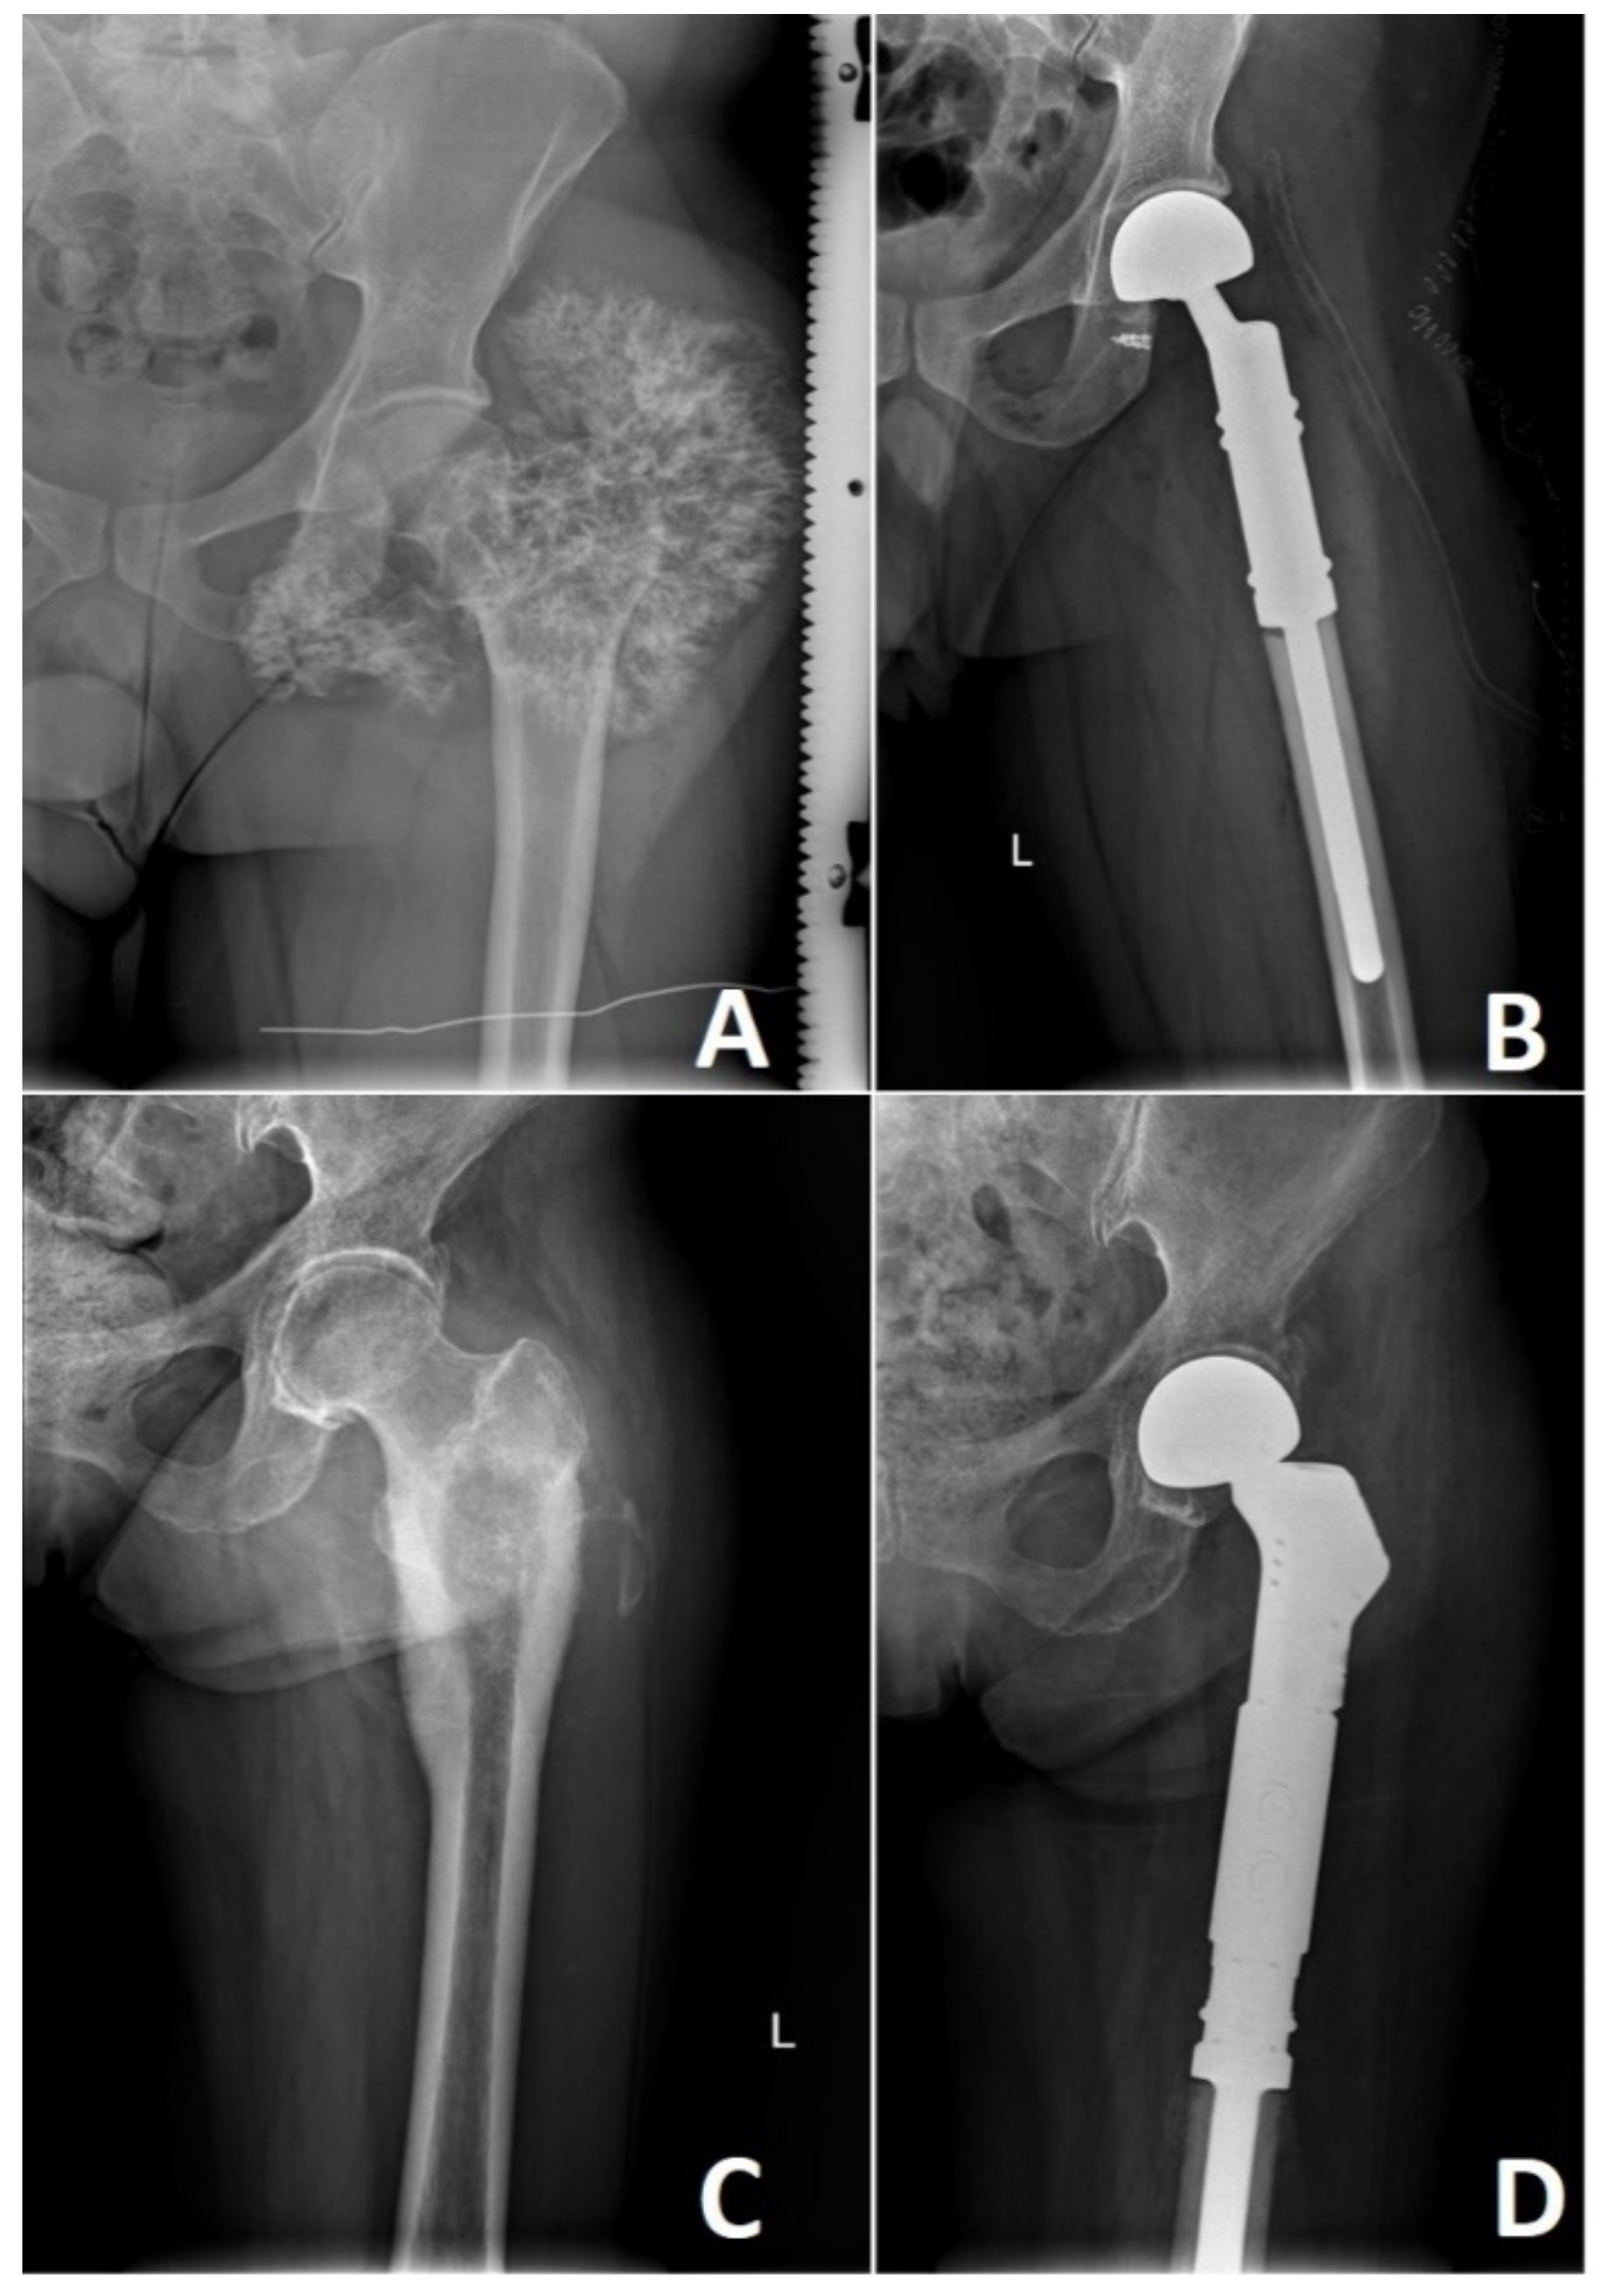

High-grade CHS lesions of the long bones usually require resection followed by limb-sparing surgery. This involves reconstruction with a modular endoprosthetic replacement, custom-made prosthesis, or bone graft reconstruction (Figure 8). In rare occasions, the size or location of these tumors necessitates a more radical approach where amputation of the affected limb remains the treatment of choice. Bingold has reported one of the first resections of the long bone in CHS, followed by a custom-designed prosthetic replacement. After resection of the proximal femoral low-grade CHS, he reported prosthetic reconstruction that spans across 43 years with several revisions [136]. Nowadays, prosthetic replacements for low-grade CHS are advocated only in locally advanced lesions where curettage or marginal resection is not an option. Prosthetic reconstruction in high-grade CHS remains to be standard with multiple options available [136,137].

Figure 8.

High grade locally advanced acral chondrosarcoma. Preoperative image of the locally advanced G2 (A) and G3 (B) chondrosarcoma of the left proximal femur. Reconstruction with modular endoprosthetic replacement (C,D). Photos by Bartłomiej Szostakowski.